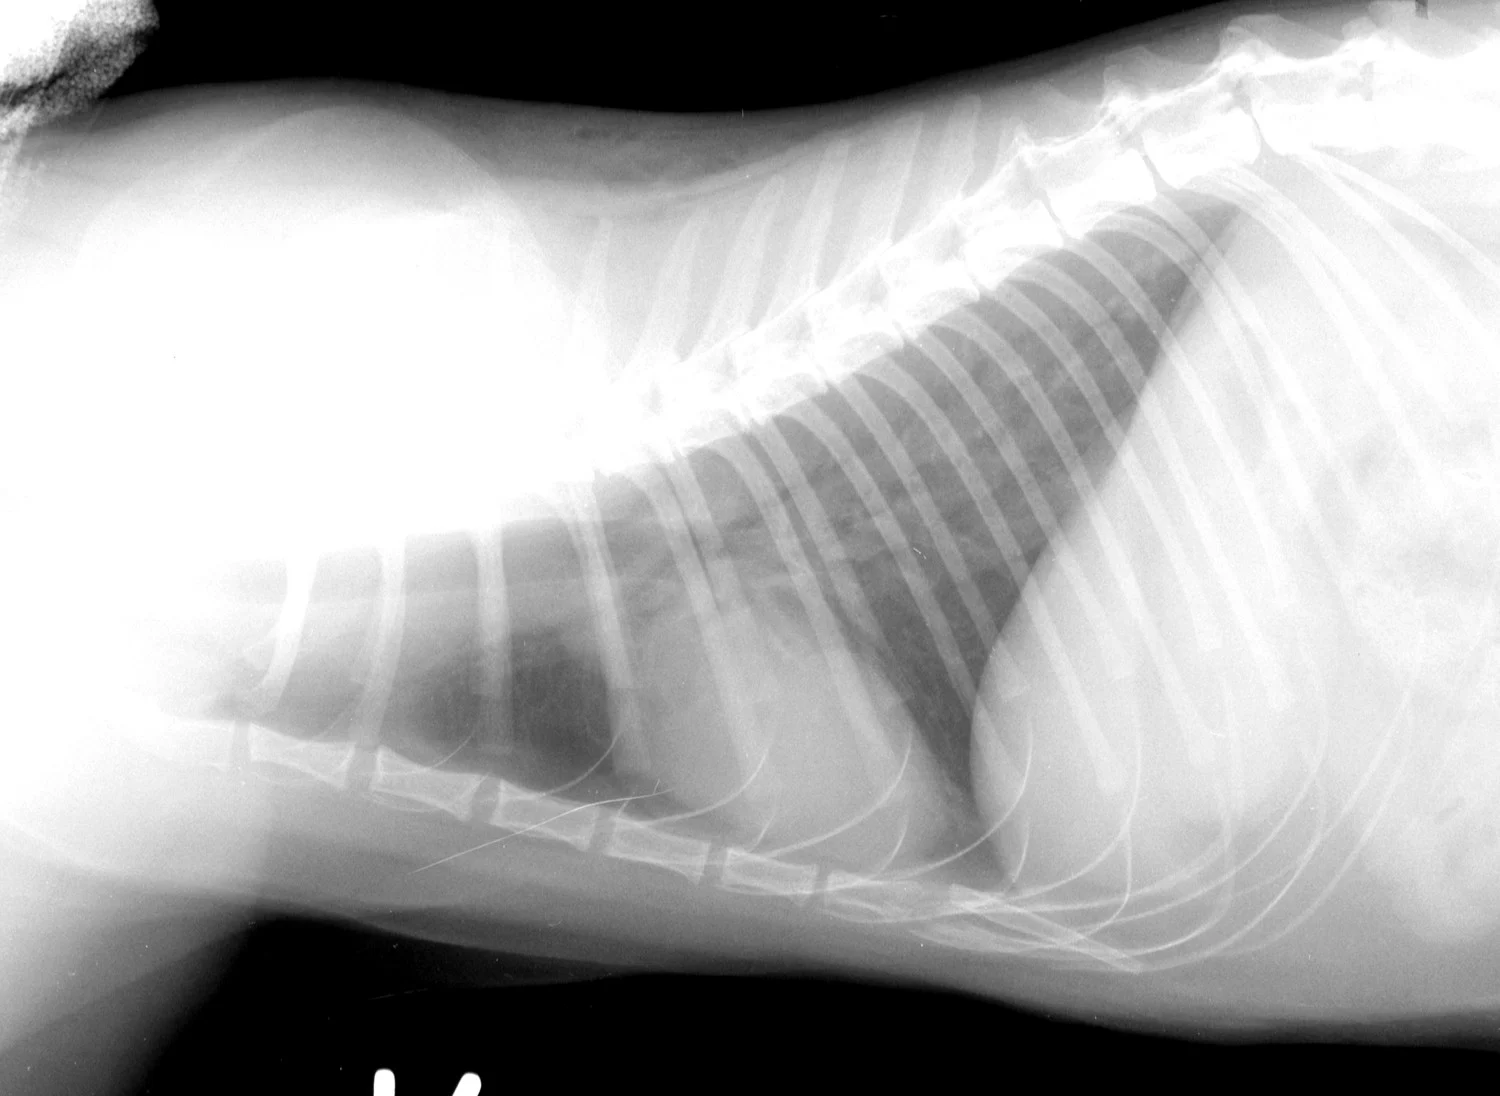

In addition to serologic tests, thoracic radiography and cardiac ultrasonography are important diagnostic tests in feline heartworm infection.

The cardiac silhouette of a cat with heartworms rarely has the "inverse D" appearance, or main pulmonary artery bulge, as seen in dogs. Cats more typically demonstrate radiographic findings compatible with feline bronchial disease ("asthma"). Nevertheless, certain findings, such as a caudal lobar pulmonary artery larger than 1.6 times the ninth rib at the ninth intercostal space, are quite suggestive of heartworm disease.

FIGURE 1A

Lateral thoracic radiograph from a cat with heartworm disease. A fine interstitial pattern is noted in the caudal lung lobes, and the chest is somewhat hyperinflated. This radiographic pattern is similar to, and thus can be confused with, that of feline bronchial disease.